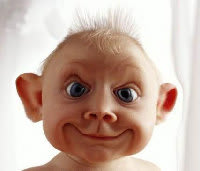

J'ai un patient avec a priori une couronne implantaire scellée dont le pilier implantaire se descelle (la couronne bouge)

2) Comment etre sur que c'est le pilier qui se devisse et pas l'implant qui a un probleme ? Y'a un test pathognomonique pour faire la difference ?

Facile, tu pinces la muqueuse Vestibulaire et linguale avec la main gauche et tu remues l'implant avec la droite.

Si tu sens que ça remue au niveau muqueux c'est l'implant.

Comme Chic22 je penche pour ça.

Il est rarissime qu'un pilier morse se dévisse, et la radio est bien moche, malgré la prolifération osseuse sur la switching platform.

Vu la radio j'ai peur pour l'implant...